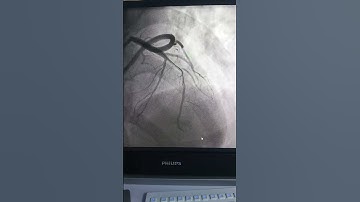

EBC 2025 - SESSION 2A - Bifurcation/LM PCI in Patients with High Bleeding Risk - WAO (CASES)